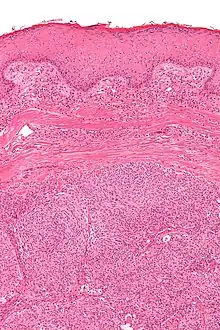

| Micrograph showing an acrospiroma. H&E stain. | |

Hidradenoma refers to a benign adnexal tumor of the apical sweat gland.[1][2] These are 1–3 cm translucent blue cystic nodules. It usually presents as a single, small skin-colored lesion, and may be considered closely related to or a variant of poromas.[3] Hidradenomas are often sub-classified based on subtle histologic differences, for example:[4]

Discussion of sweat gland tumors can be difficult and confusing due to the complex classification and redundant terminology used to describe the same tumors. For example, acrospiroma and hidradenoma are synonymous, and sometimes the term acrospiroma is used to generally describe benign sweat gland tumors. In addition, a single lesion may contain a mixture of cell-types.[2] There has also been a change in understanding about how tumors that were previously believed to strictly derive from specific sweat gland types may, in fact, derive from both eccrine or apocrine glands.[5][6]